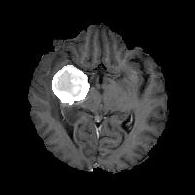

We argue that the sub-optimal paradigm of processing different abstractions within a single CNN pipeline can be remedied through the effective processing of information in a structured manner. Consequently, we devise strategies for disentangling the edge and texture information within a single training pipeline. Figure 2 illustrates how our proposed module, dubbed EG-CNN, can be paired with any existing CNN encoder-decoder to improve segmentation quality near intensity edges. We have applied our EG-CNN to the tasks of brain and liver tumor segmentation in medical images (Figure 3).

(1) Brain MR (2) Liver MR (3) Liver CT (4) Lung CT